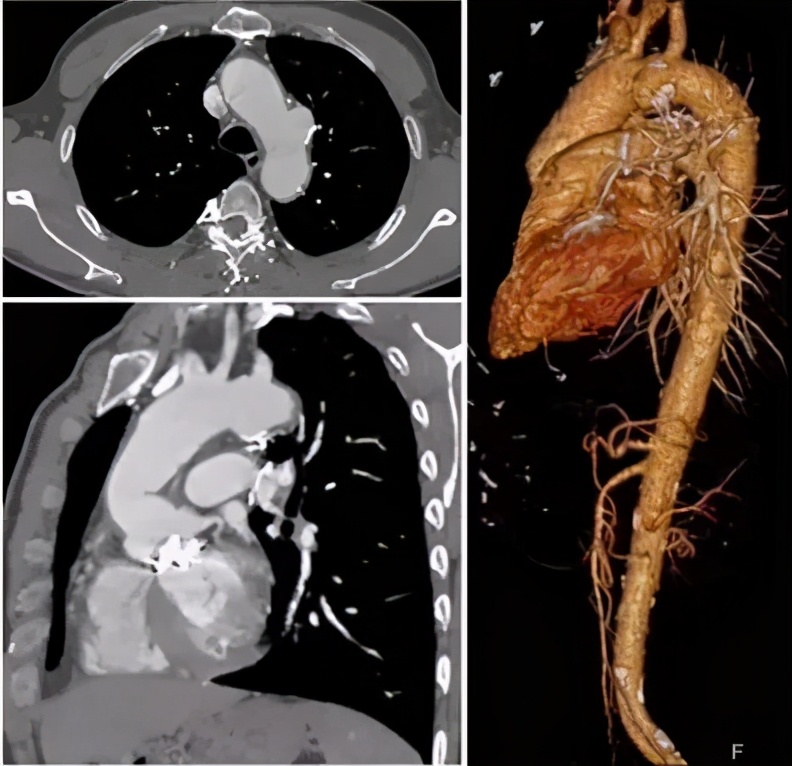

病例1(男性,67岁)

主诉:眩晕1月余,胸闷加重10天余。

既往史:高血压、糖尿病。

手术史:28年前行“胰腺坏死组织清除术”;19年前因“升主动脉瘤+AI(重度)”行Wheat手术;10年前行冠状动脉支架植入术。

查体及实验室检查:无特殊。

心脏彩超:(-)。

手术策略:弓上三分支原位开窗+主动脉腔内修复术。

手术步骤:股-颈动脉转流;释放远端限制性支架+近端主体支架;无名动脉原位开窗+支架植入;左颈总动脉原位开窗+支架植入;左锁骨下动脉原位开窗+支架植入。

手术要点:注意支架直径的选择与人工血管直径及预计锚定位置的关系;近端锚定区位置判断及预估裸支架位置与人工血管皱褶、冠脉开口的关系;术中超硬导丝的走行,支架输送鞘tip头长度、右冠吻合口及人工瓣膜的保护。